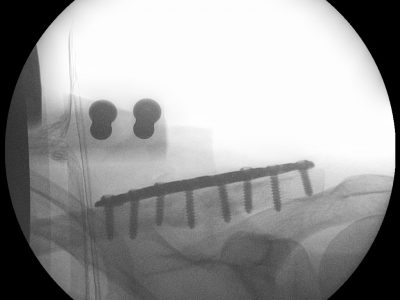

Παρακάτω παρατίθενται ακτινογραφίες καταγμάτων του άνω άκρου που αντιμετωπίζονται με εσωτερική οστεοσύνθεση ή επανορθωτική χειρουργική με αρθροπλαστική.